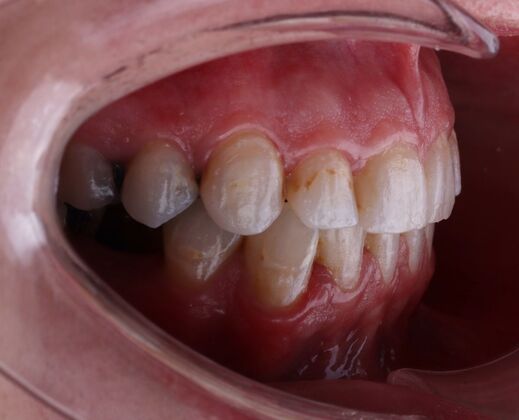

Porcelain Veneers: Michelle

Description

A smile is a very important part of one's appearance and is often the first thing people notice. Every person has a different color of teeth, and many have a different shape. Luckily there is a solution to improve your smile: Veneers!